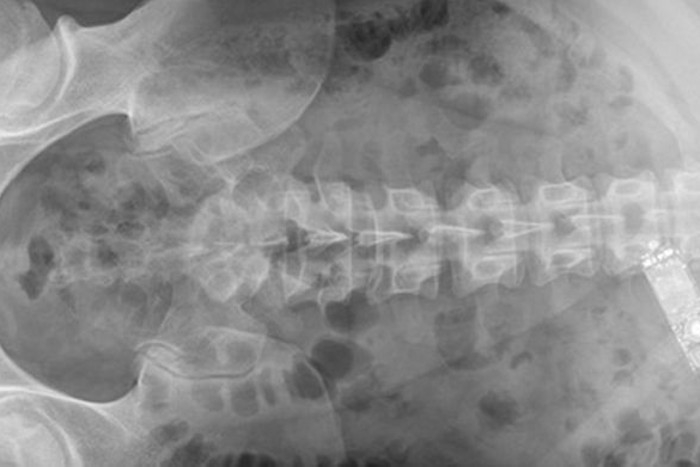

डॉक्टरों को उस वक्त अजीबो गरीब स्थिति का सामना करना पड़ा, जब ऑयरलैंड के 29 वर्षीय कैदी ने मोबाइल फोन को ही निगल लिया। दरअसल, कैदी को चार घंटे से लगातार उल्टियां हो रही थी, जिस पर उसे पुलिस हॉस्पिटल ले गई। हॉस्पिटल में भर्ती कराने के बाद एक्स-रे के जरिए पता चला कि कैदी के पेट में मोबाइल है।

इस पर डॉक्टरों ने एंडोस्कोपिक टूल के जरिए कैदी को बेहोश कर मोबाइल फोन को गले के जरिए निकालने की कोशिश की लेकिन नाकाम होने पर उन्हें ऑपरेशन का सहारा लेना पड़ा। पेट से ऑपरेशन के जरिए निकाला गया मोबाइल फोन 6.8 × 2.3 × 1.1 cm का था।

ऑपरेशन करने वाली ऑस्ट्रेलिया के डबलिन स्थित द एडीलेड एंड मेथ हॉस्पिटल के डिपार्टमेंट ऑफ सर्जरी की टीम ने बताया कि हमने सोचा कि मोबाइल को आसानी से शरीर से बाहर निकाला जा सकता है, लेकिन 18 घंटों की मशक्कत के बाद एक्स-रे से पता लगा कि मोबाइल टस से मस नहीं हुआ।

सबसे पहले डॉक्टरों ने एंडोस्कोपिक टूल की मदद ली लेकिन काफी कोशिशों के बाद जब यह पता चला कि मोबाइल ऐसे जगह पर फंसा है कि उसे निकालने से अंदर कुछ नुकसान हो सकता है।